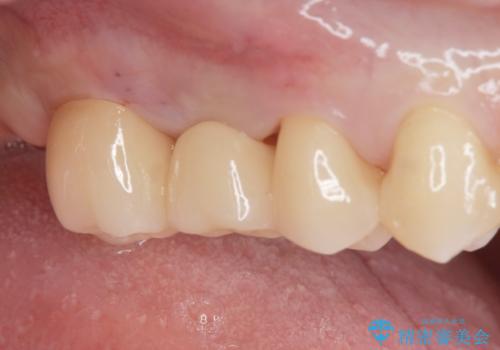

適合の良いブリッジが入りました。

歯の傾きを改善することにより食べ物が詰まりにくくなりました。

白い被せ物が入り、満足して頂けました。